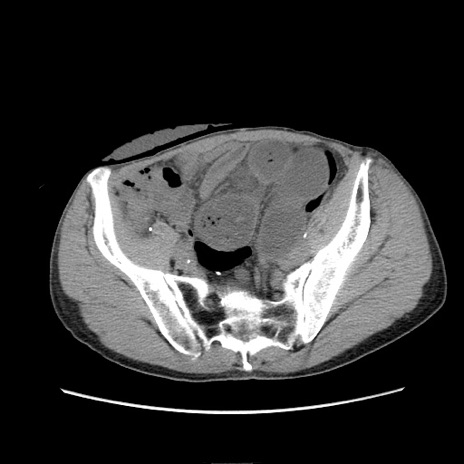

症例11(横断像)

【症例】 60歳代男性

【主訴】 下腹部痛

【現病歴】 本日夜中より下腹部痛の症状認め、受診。

【既往歴】 膀胱癌(膀胱全摘+尿管皮膚瘻術) 、胃癌術後

【身体所見】 BT 35.3℃、PR 58/min、BP 136/98mHg、腹部平坦、軟、腸蠕動音±、ストマ留置あり、左上腹部~正中部に圧痛あり、反跳痛なし。

【データ】WBC 5100、CRP0.01